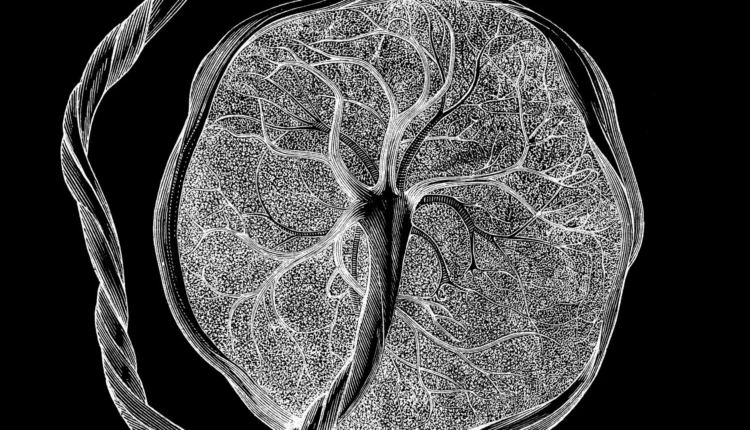

Επιστήμονες αποκάλυψαν έναν λεπτομερή «άτλαντα» του πλακούντα και της μήτρας, δείχνοντας πώς αυτοί οι μοναδικοί ιστοί αναπτύσσονται και εξελίσσονται καθ’ όλη τη διάρκεια της εγκυμοσύνης για να υποστηρίξουν ένα αναπτυσσόμενο έμβρυο.

«Η μεγαλύτερη διαφορά είναι ότι εξετάζουμε ολόκληρη τη χρονική πορεία» από την πρώιμη εγκυμοσύνη έως τη γέννηση, δήλωσε ο Li. Ο νέος άτλαντας ενσωματώνει δεδομένα από ιστούς που συλλέχθηκαν μεταξύ της 5ης και της 39ης εβδομάδας κύησης και στη συνέχεια αποθηκεύτηκαν σε τράπεζες ιστών στο UCSF και στο Πανεπιστήμιο του Στάνφορντ.

Το εργαστήριο του Li αναλύει ιστούς λεπτομερώς, στην ανάλυση μεμονωμένων κυττάρων, με την ανάπτυξη του πλακούντα να αποτελεί μία από τις κύριες ερευνητικές εστίασης της ομάδας. Ο νέος τους άτλαντας ενσωματώνει στιγμιότυπα του ποιες γονιδιακές εκφράσεις ήταν ενεργές και ποιες πρωτεΐνες ήταν παρούσες στα αναλυόμενα κύτταρα σε μια δεδομένη φάση της εγκυμοσύνης. Εξετάζει επίσης την «προσβασιμότητα της χρωματίνης», η οποία αντικατοπτρίζει πώς συσκευάζονται τα μόρια DNA μέσα στο κύτταρο και ποια γονίδια μπορούν να ενεργοποιηθούν σε μια δεδομένη στιγμή.

Συνολικά, η ομάδα ανάλυσε περίπου 1,2 εκατομμύρια κύτταρα πλακούντα και μήτρας, συμπεριλαμβανομένων 200.000 μεμονωμένων κυττάρων και 1 εκατομμυρίου κυττάρων ενσωματωμένων στις αρχικές τους θέσεις εντός του ιστού.